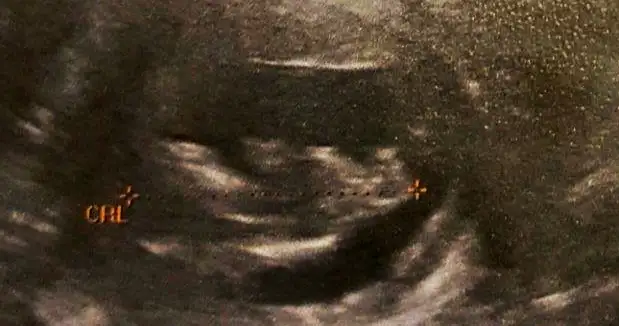

merhaba Havalianne__ . Bana da bir tahminde bulunabilir misin? :)

12 haftalık usg.

Eklentiler

• 20160818_112811.webp

16,8 KB · Görüntüleme: 46

• 20160816_180700.webp

21,7 KB · Görüntüleme: 49